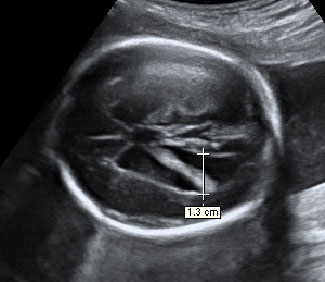

Las ecografías en 2D y en 3D en la semana 20 de embarazo permite diagnosticar algunas malformaciones congénitas fetales, como el labio leporino, que se visualiza en estas imágenes.